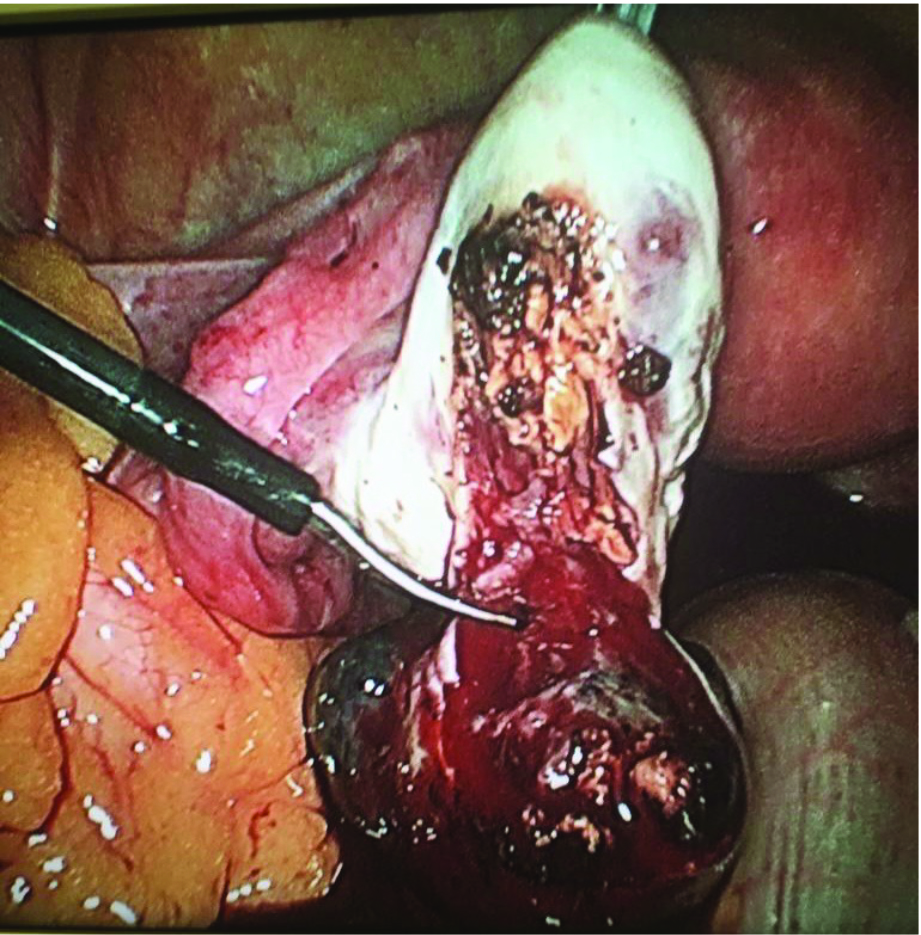

A day after the third level of beta hCG, the patient began complaining of severe lower abdominal pains and became hypotensive with blood pressure 80/45. A laparoscopy was performed due to severe pain and hypotension. Ectopic pregnancy was identified over the left ovary. Uterus, bilateral fallopian and right ovary were normal. There was pelvic haemoperitoneum and no signs of adhesions or Fitz-Hugh-Curtis syndrome (FHCS). Laparoscopic removal of left ovarian ectopic pregnancy was performed by diathermy scissors.

Postoperative period was uneventful and the patient conceived seven months later and delivered normally a full term baby. Histopathological examination of ectopic mass showed left ovarian ectopic pregnancy.